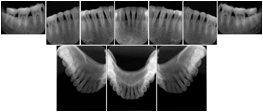

Intra-oral radiography typically involves acquisition of multiple images of various parts of the dentition. Many digital radiographic systems offer customized templates that are used for displaying the images in a study on the screen. These templates may also be referred to as mounts or view sets. The Structured Display Object represents a standard method of encoding and exchanging the layout and intended display of Structured Displays. A structured display object created in this manner could be stored with a study and exchanged with images to allow for complete reproduction of the original exam.

2. A patient requests cosmetic surgery to enhance their facial appearance. The case requires consultation between an orthodontist in New York and an oral surgeon in California. The cephalometric series of 2D projections constructed from a volumetric CT data set that is used for the discussion is arranged by a Structured Display for transfer between the two practitioners.

Cephalometric Series Structured Display

Figure OO-2. Cephalometric Series Structured Display